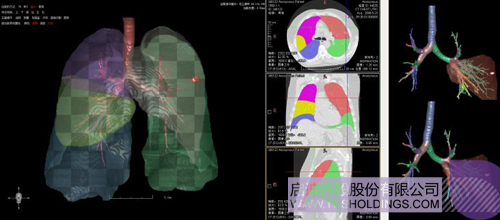

数字肺产品肺癌计算机辅助诊断

医疗影像智能分析是指运用人工智能技术、计算机视觉技术以及计算几何技术对医疗影像进行自动分析,帮助医生定位病症、分析、跟踪病情,并通过量化数据辅助医生做出诊断,目前其旗舰产品“数字肺”已经覆盖多种肺部疾病的早期检测、诊断、跟踪、术前规划等完整的医疗流程。在临床实践中,超过80%的医疗数据来自医疗影像,这些影像数据通常需要专业医生进行解读,工作的重复性高、效率偏低。如果能够运用智能影像分析技术,同时结合临床表现以及既往病例进行全面分析,那么就可以大幅度提升影像诊断效率和准确性,让专业医生的宝贵时间集中在复杂病情的诊断和治疗等环节。

神州德信在医疗影像人工智能方面的核心技术为:智能影像=机器学习+计算/微分几何+深度学习。

(1)计算/微分几何用于分析、量化、可视化影像中所变现的各类组织以及病变等形态特征,机器学习主要对影像以及相关病变进行分类等定性分析并辅助一些定量分析,是服务临床的一个重要模块或者环节但不是唯一的环节。上述两者在影像分析中互为补充、彼此增强,构建了神州德信智能影像分析的技术基础。

(2)在整个智能影像分析中,核心技术建立在对医学图像深刻理解的基础之上,相关几何分析技术可以对数据进行有效增强和预处理,提升目前深度学习的学习能力、尽可能降低深度学习对样本规模、多样性和标注的要求,有效改变当前以深度学习为代表的“人工智能”重在 “人工”而不是“智能”的特点。

完整的三维影像智能分析技术;

完整的三维可视化以及相关建模、几何分析技术;

肺动脉栓塞辅助诊断